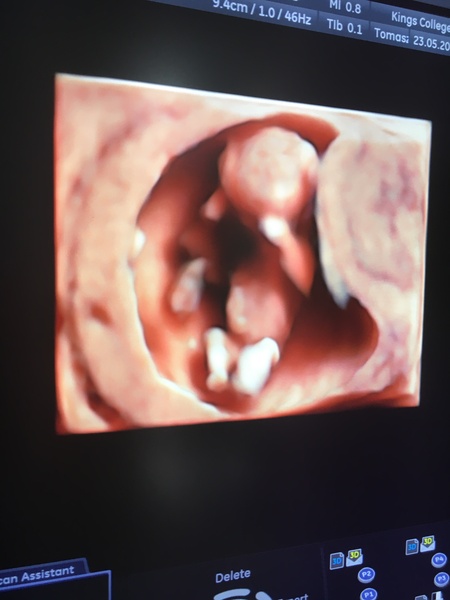

0lgaDaPolga · 23/05/2018 20:33

Scan here today too. All good and even got a 3D photo! I’ve been adjusted to 12+6 so now due 29th November.

If anyone wants to join us on the Facebook group drop me a pm and I’ll add you Smile

0lgaDaPolga · 23/05/2018 20:57

No I didn’t @magicalcreatures I’m really lucky to be having my scans at Kings College in London as it’s a really state of the art facility and they seem to have amazing equipment for the scans! They did 3D on the 20 week scan with my son and that was lovely as you could see his little face at that point

MagicalCreatures · 23/05/2018 22:04

@0lgaDaPolga that’s incredible. Wish all the hospitals were like that x x